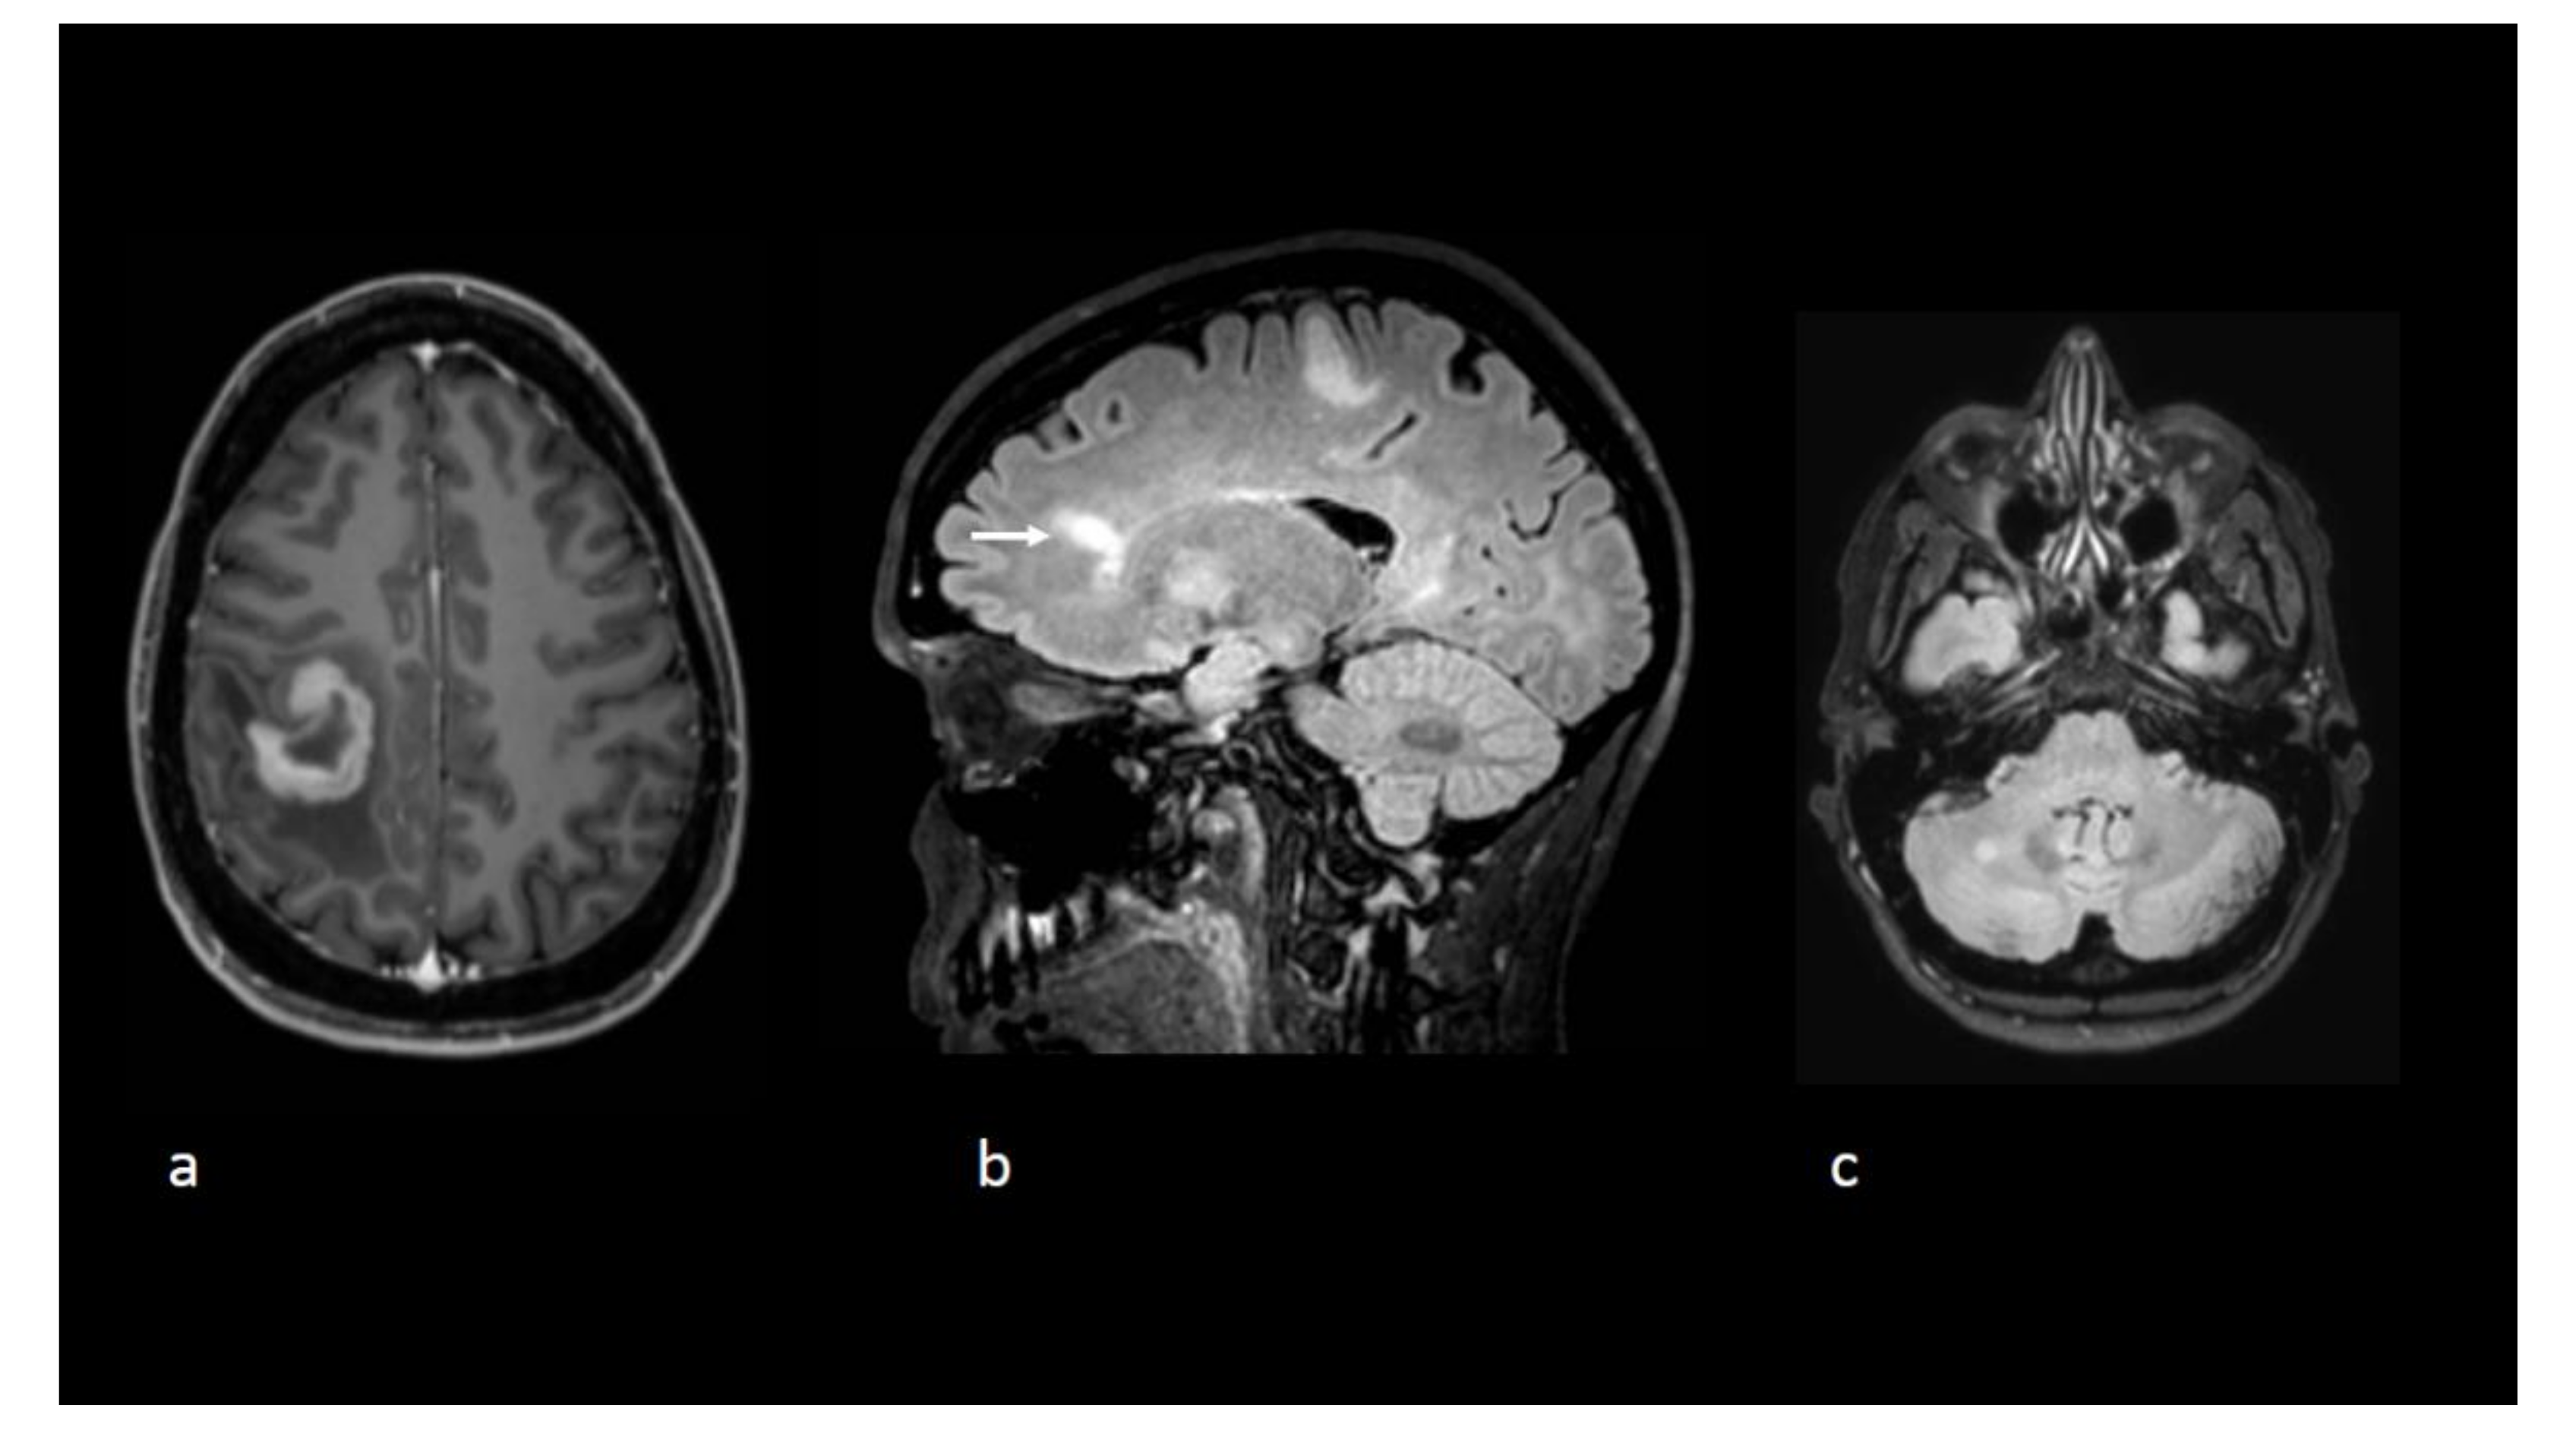

Figure 1.

Axial T1-weighted postgadolinium image (a) reveals a tumefactive lesion centred on the central sulcus with a thick open-ring enhancement pattern before initiation of natalizumab. Sagittal (b) and axial (c). Fluid-attenuated inversion recovery (FLAIR) sequences show other nonenhancing lesions including one with a Dawson’s fingers appearance (white arrow).